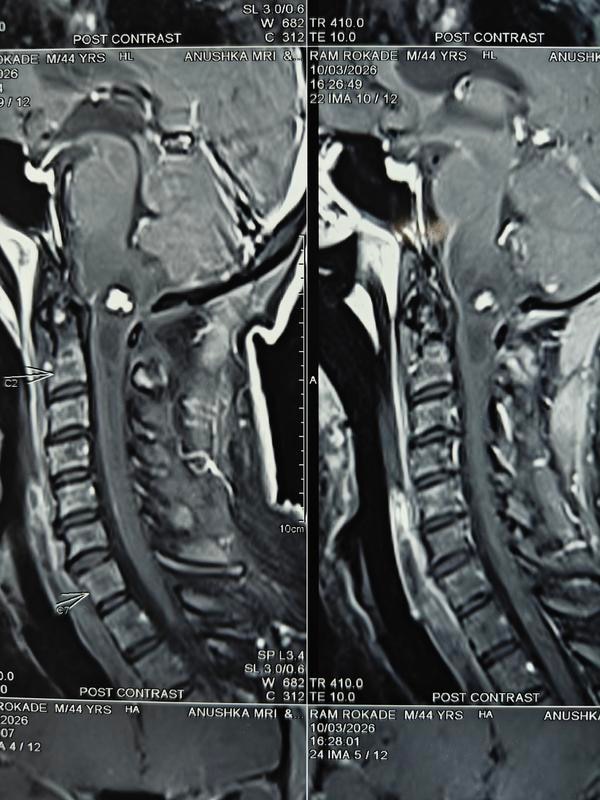

How serious is spinal surgery?Back surgery can carry higher risks than some other types of surgery because it is done closer to the nervous system. The most serious of these risks include paralysis and infections. Even with a successful surgery, the recovery time can be long.